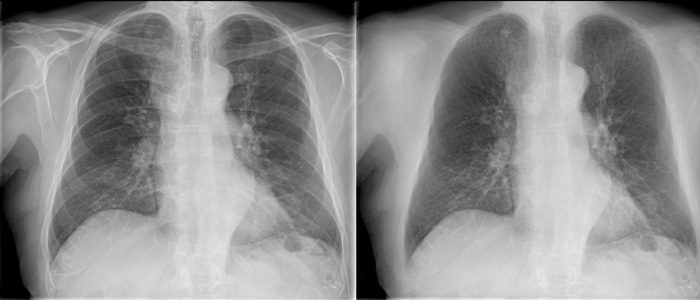

Innovative image enhancement technology designed to increase the clarity of adult erect chest radiographs by suppressing bones on digital images.